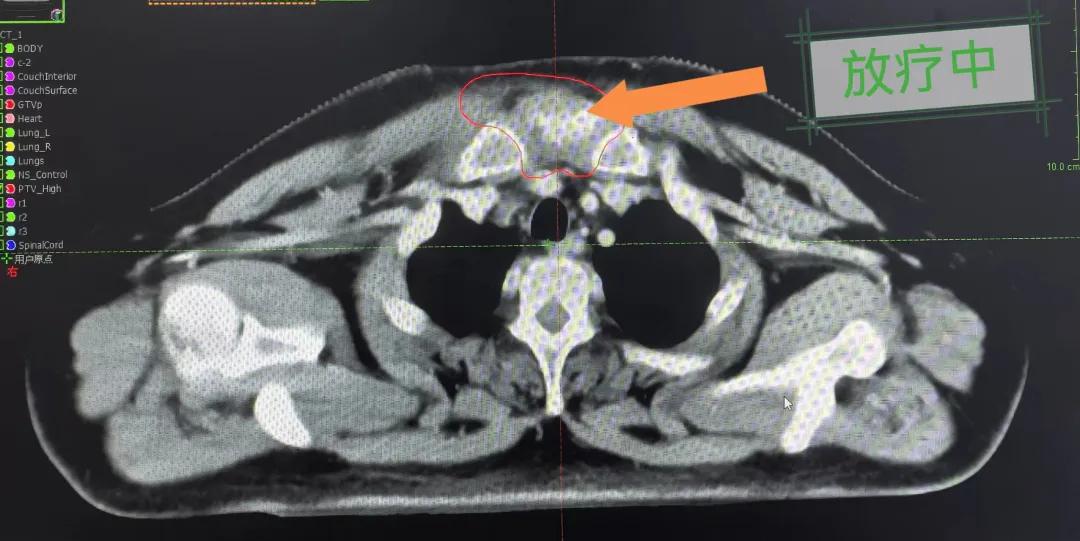

隨后,趙亮主任帶領(lǐng)放療團(tuán)隊(duì)以最快的速度完成了患者的放射治療計(jì)劃,在保證放療精準(zhǔn)打擊腫瘤的同時(shí),利用先進(jìn)的三維立體精確放療技術(shù),最大限度的避免心臟、肺部的損傷發(fā)生,整體治療精準(zhǔn)度達(dá)到1mm以內(nèi)。經(jīng)過10次的放射治療后,患者疼痛已明顯減輕,胸部腫物肉眼可見的縮小,患者及家屬臉上終于露出久違的笑臉。

治療期間,患者沒有出現(xiàn)明顯不適,治療結(jié)束后,患者胸壁腫物由最初8cm縮小至約1cm,后患者至外科行手術(shù)治療。